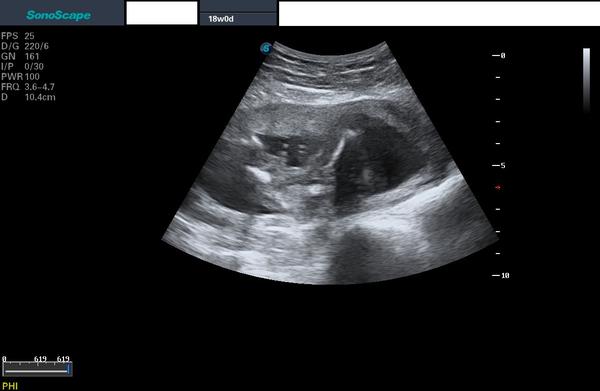

na flashku mi doktor v 18. týdnu těhotenství nahrál několik fotek z ultrazvuku a já nemůžu přijít na to, co je na téhle 😀 přijde mi to jen jako změť fleků. Co byste řekli, že to je? Nějaký detail?

Ja bych rekla lezici miminko, vlevo hlavicka, to vyrazny rucicky, takovy to vroubkovany nahoru pupecnik a pak nozky 🙂

Jak rika @petruuushkaaa 🙂 presne, levo hlavicka, pak kousek doprava rucicka a pokrcena nozicka tvar ^ 🙂